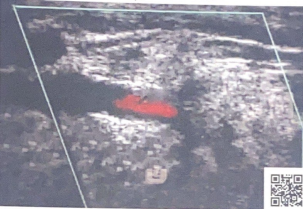

Patient presents to ultrasound department for preoperative work-up. Patient scheduled to have coronary artery bypass graft (CABG) in two days. Patient has HX of peripheral vascular disease, smoking, HTN and hyperlipidemia. You obtain this image. Consider following questions.

1. Is it possible to have plaque producing stenosis without symptoms?

2. What are the risk factors for atherosclerosis in this patient presentation?

3. Is this image diagnostic for hemodynamically significant stenosis? Why or why not.

Yes

Hx of peripheral vascular disease, smoking, HTN, hyperlipidemia. (Also has CAD because they are here for pre op for CABG)

No because power doppler only shows presence of flow and no velocity information